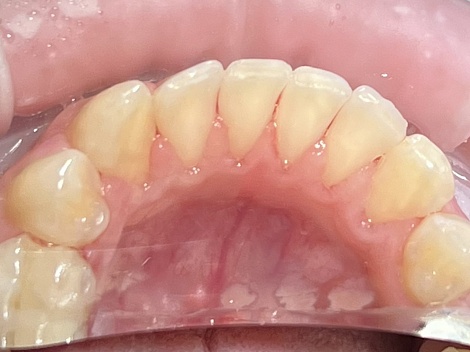

Комплексная профессиональная гигиена полости рта с последующей реминерализацией эмали

До

После

Услуги:

Гигиена зубов и полости рта ,

Чистка зубов

Заболевания:

Стоматология

«Все свои!» м.Люблино